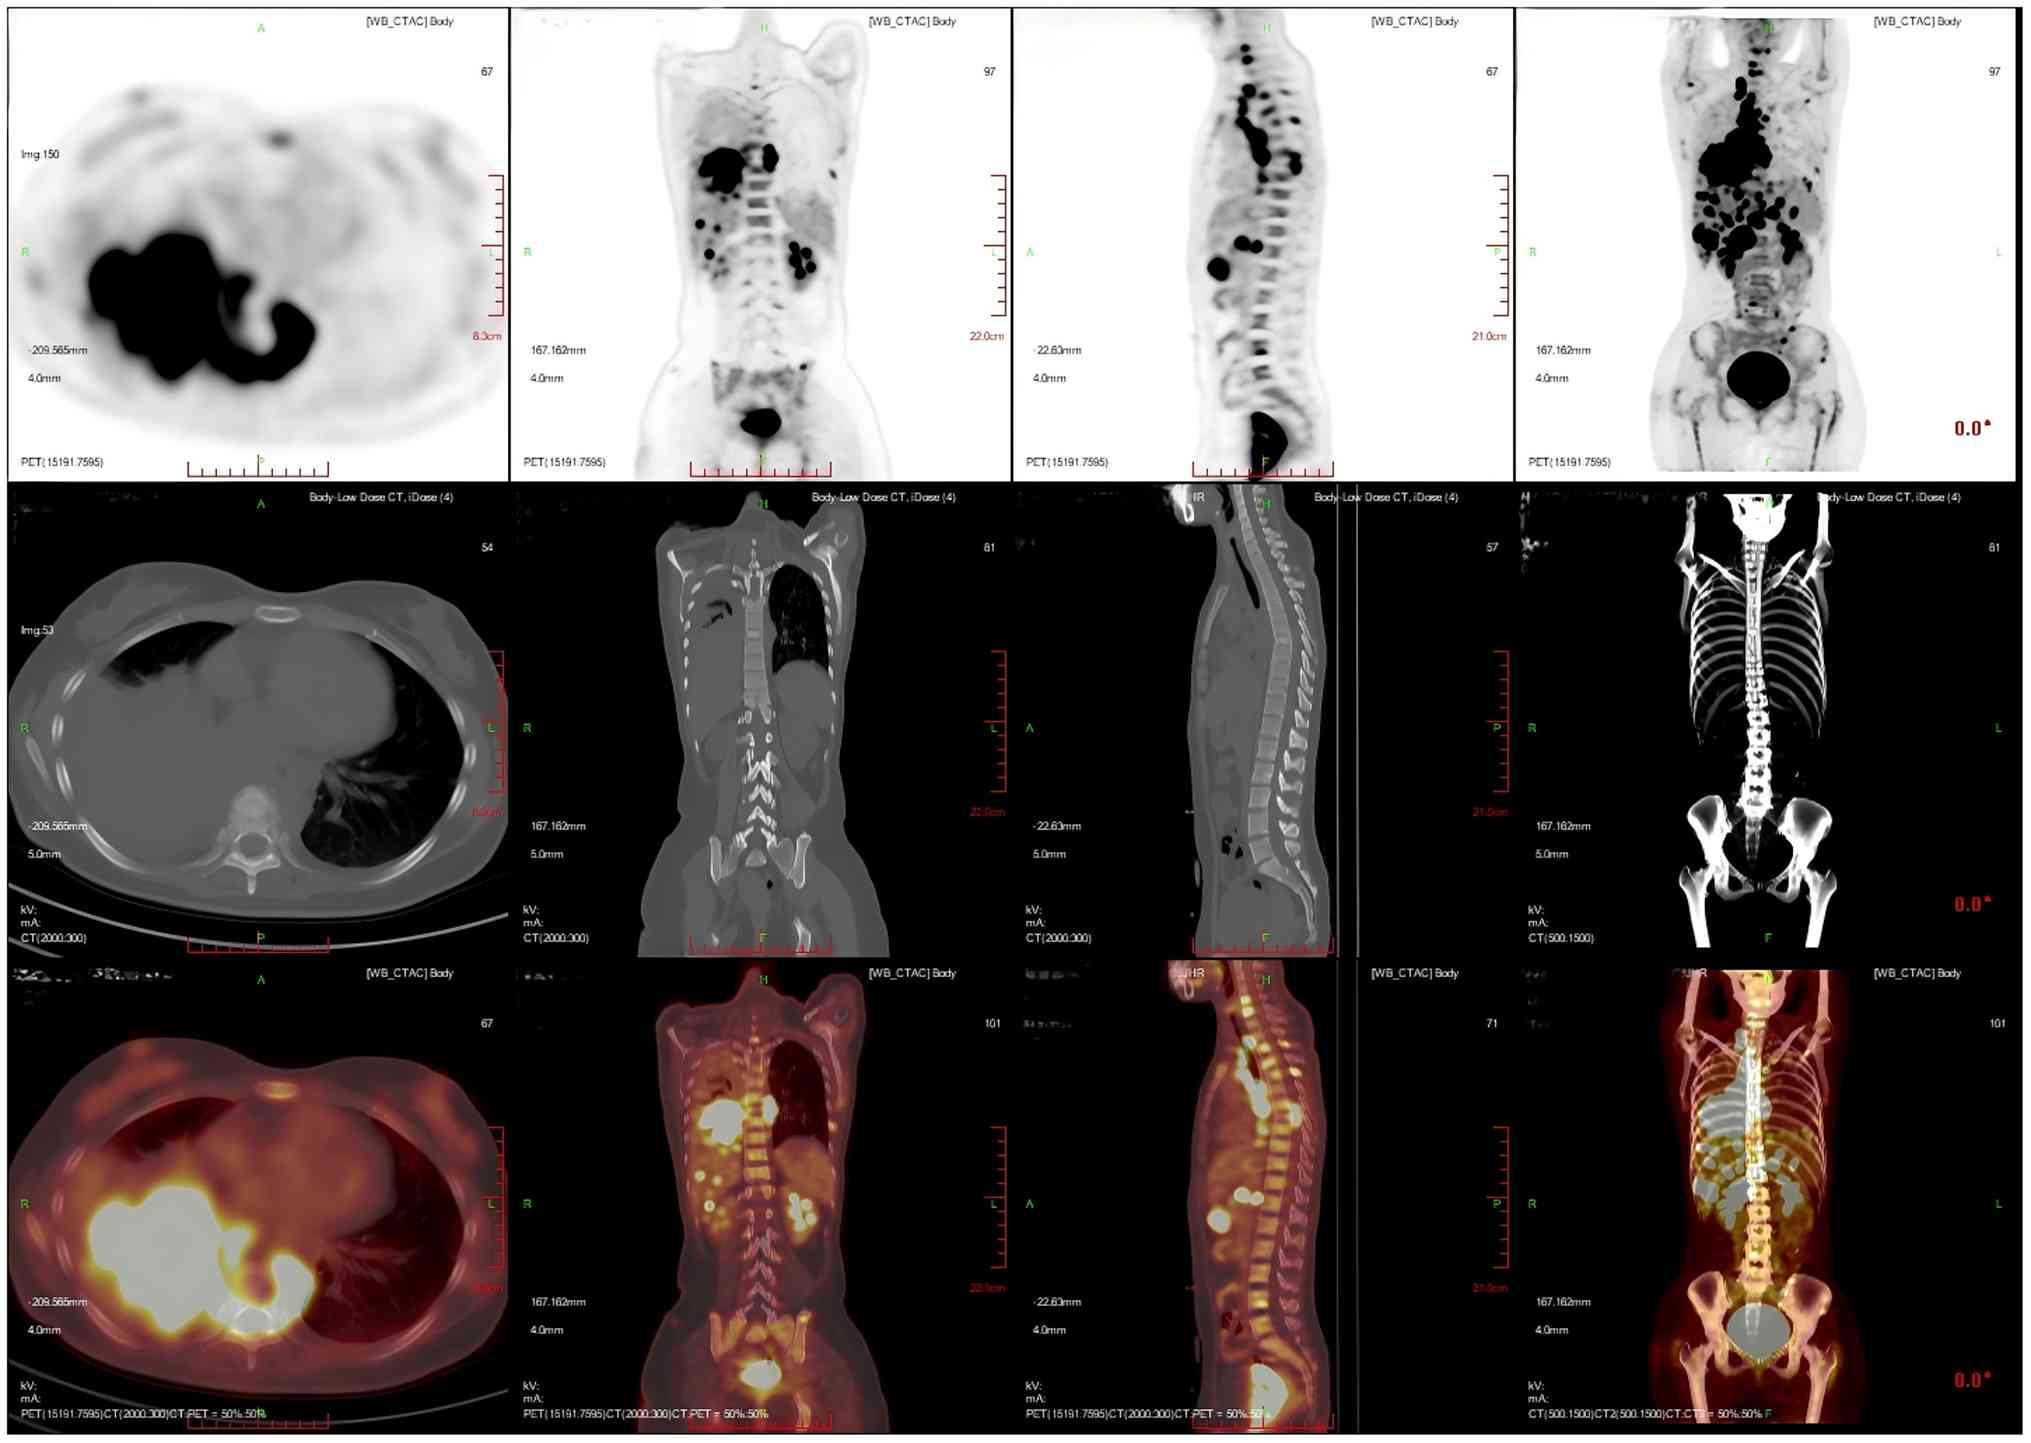

After 1 month, the patient developed numbness and discomfort below the waist, weakness of both lower limbs and limitations to lifting. To clarify the changes in the condition of the patient, positron emission tomography/CT (PET/CT) was performed. PET/CT images showed that an irregular mass-like hyperdense shadow was detected in the right lung hilar and the middle and lower lobes of the right lung; no normal lung tissue was seen, the lesion crossed the interlobular pleura and invaded the upper lobe of the right lung, and the corresponding area on PET showed a mass-like radiolucency focus with an maximum standardized uptake value (SUVmax) of 25.8 (Fig. 5). Multiple enlarged and swollen lymph nodes were detected in the mediastinum, bilateral pulmonary hilar region, bilateral diaphragmatic pedicle and right cardiogenic angle area, partially fused in the form of a mass. PET showed a mass of radiolucent foci in the corresponding areas, and the SUVmax of the hypermetabolic area under the bronchus was measured to be 21.4. Thickening of the right pleura was observed, an arcuate fluid density shadow was seen in the thoracic cavity and mild radiolucent uptake was visible in the area of pleural effusion on the right side of the chest cavity (Fig. 6). The liver was full, with diffuse low-density nodules and masses of varying sizes within it, and PET showed nodular and mass-like radioactivity uptake in the corresponding areas. The low-density mass in the S4 segment of the liver was measured to be ~5.0×4.4 cm in size, with an SUVmax of 20.0. Several enlarged lymph nodes were observed in the portal region of the liver, which had fused to form a mass. PET scans showed mass-like radioactivity uptake in the corresponding areas, with a SUVmax of 20.2 (Fig. 7). Multiple nodular and striated radiographic uptake of the right humeral head, multiple parts of the sternum, bilateral scapulae, cervical, thoracic and lumbar vertebral bodies, part of the accessory bones, the two flanks of the sacrum, multiple parts of the pelvic bone and the proximal segment of the left femur were noted. CT demonstrated an inhomogeneous increase in the density of the bone at the corresponding sites, discontinuity of the cortex in some of the neighboring bones, flattening of the seventh thoracic vertebral body, morphological disorders and an increase in the peripheral soft-tissue shadows. A high metabolic area was measured in the seventh thoracic vertebral body, with an SUVmax of 20.4 (Fig. 8).

Multiplanar 18F-FDG PET/CT imaging of

the patient's hypermetabolic mass lesion in the right lung. An

irregular mass-like hyperdense shadow was detected in the right

lung hilar and the middle and lower lobes of the right lung; no

normal lung tissue was seen, the lesion crossed the interlobular

pleura and invaded the upper lobe of the right lung, and the

corresponding area on positron emission tomography showed a

mass-like radiolucency focus with a SUVmax of 25.8.

Imaging modalities: PET (top row); CT (middle row); PET/CT fusion

imaging (bottom row). Imaging planes: Axial plane (first column)

showing cross-sectional views, with transaxial details of the right

pulmonary lesion. Coronal plane (second column): Frontal views

displaying craniocaudal extension of the lesion across right lung

lobes. Sagittal plane (third column): Lateral views illustrating

anteroposterior localization of the lesion relative to the hilum.

Volume-rendered CT (fourth column, middle row); a 3D reconstructed

thoracic CT scan depicting the bony thorax and spatial context of

the pulmonary lesion. CT, computed tomography; PET, positron

emission tomography.

Figure 5.

Multiplanar 18F-FDG PET/CT imaging of the patient's hypermetabolic mass lesion in the right lung. An irregular mass-like hyperdense shadow was detected in the right lung hilar and the middle and lower lobes of the right lung; no normal lung tissue was seen, the lesion crossed the interlobular pleura and invaded the upper lobe of the right lung, and the corresponding area on positron emission tomography showed a mass-like radiolucency focus with a SUVmax of 25.8. Imaging modalities: PET (top row); CT (middle row); PET/CT fusion imaging (bottom row). Imaging planes: Axial plane (first column) showing cross-sectional views, with transaxial details of the right pulmonary lesion. Coronal plane (second column): Frontal views displaying craniocaudal extension of the lesion across right lung lobes. Sagittal plane (third column): Lateral views illustrating anteroposterior localization of the lesion relative to the hilum. Volume-rendered CT (fourth column, middle row); a 3D reconstructed thoracic CT scan depicting the bony thorax and spatial context of the pulmonary lesion. CT, computed tomography; PET, positron emission tomography.